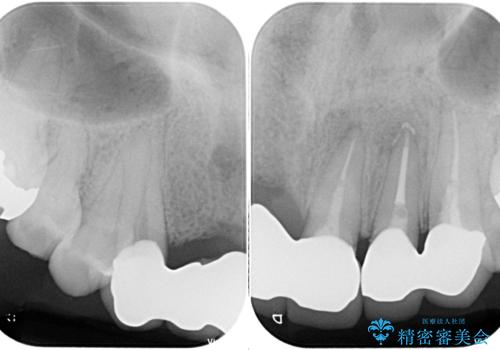

受け口を無理やりブリッジで改善したことで、支台歯の1本は歯根が破折しており抜歯が必要な状態でした。

根管治療がされている歯の一部には根尖部の違和感があり、根管治療が必要と判断されました。

抜歯および根管治療を実施した後にオールセラミッククラウンにて補綴することとしました。